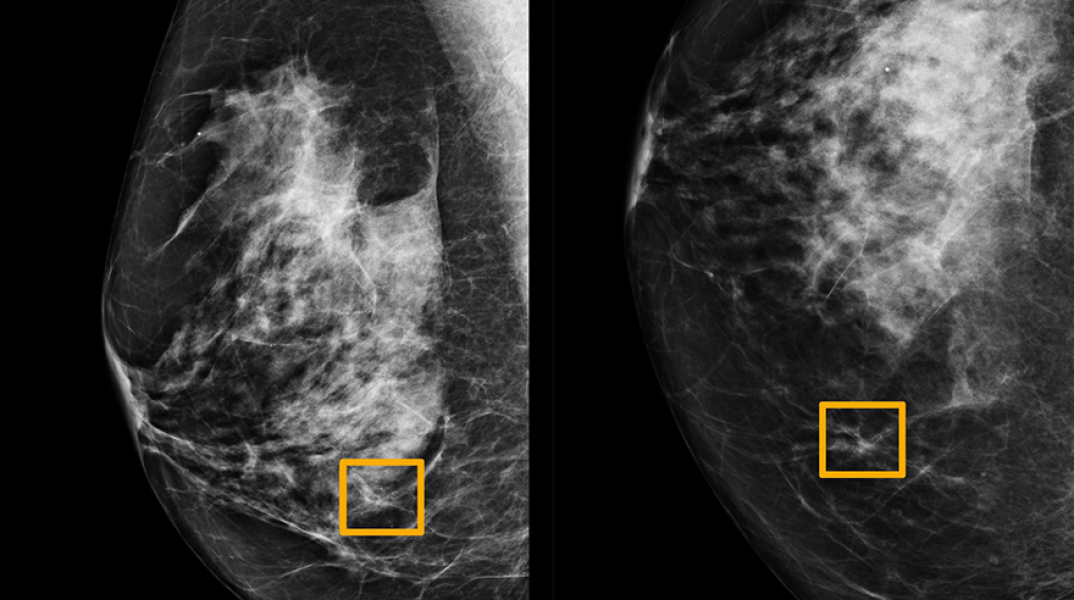

Πρόγραμμα τεχνητής νοημοσύνης από το Google Health φέρεται να εντοπίζει καλύτερα τον καρκίνο του μαστού στις μαστογραφίες από ό,τι οι ειδικοί γιατροί.

Πρόγραμμα τεχνητής νοημοσύνης (AI) φέρεται να εντοπίζει με μεγαλύτερη ακρίβεια τον καρκίνο του μαστού στις μαστογραφίες από ό,τι οι ειδικοί ακτινολόγοι.

Δημοσίευμα στον βρετανικό Guardian αναφέρει ότι το σύστημα AI, το οποίο έχει αναπτυχθεί από το Google Health, εντόπισε καρκίνους που οι ακτινολόγοι παράβλεψαν.

Σύμφωνα με το δημοσίευμα η ανάλυση των μαστογραφιών μέσω της τεχνολογίας μείωσε το ενδεχόμενο λάθους τόσο στο θετικό αποτέλεσμα, κατά το οποίο διαγιγνώσκεται καρκίνος σε υγιή άτομα λανθασμένα, όσο και στο αρνητικό αποτέλεσμα, κατά το οποίο δεν εντοπίζεται ο καρκίνος ενός ασθενή. Το σύστημα μείωσε τα ψευδώς θετικά αποτελέσματα κατά 5,7% στις Η.Π.Α., σύμφωνα με στοιχεία που περιλαμβάνουν πάνω από 28.000 μαστογραφίες που πραγματοποιήθηκαν εκεί και στο Ηνωμένο Βασίλειο.

«Είναι μια σημαντική απόδειξη το πώς μπορούν αυτές οι τεχνολογίες να βοηθήσουν αλλά και να ενισχύσουν το ανθρώπινο δυναμικό στον τομέα της υγείας», δήλωσε ο επικεφαλής του Google Health στο Ηνωμένο Βασίλειο, Ντόμινικ Κινγκ. «Η τεχνητή νοημοσύνης μας λέει: 'Πιστεύω ότι εδώ μπορεί να υπάρχει θέμα. Να το ελέγξουμε;'», πρόσθεσε.